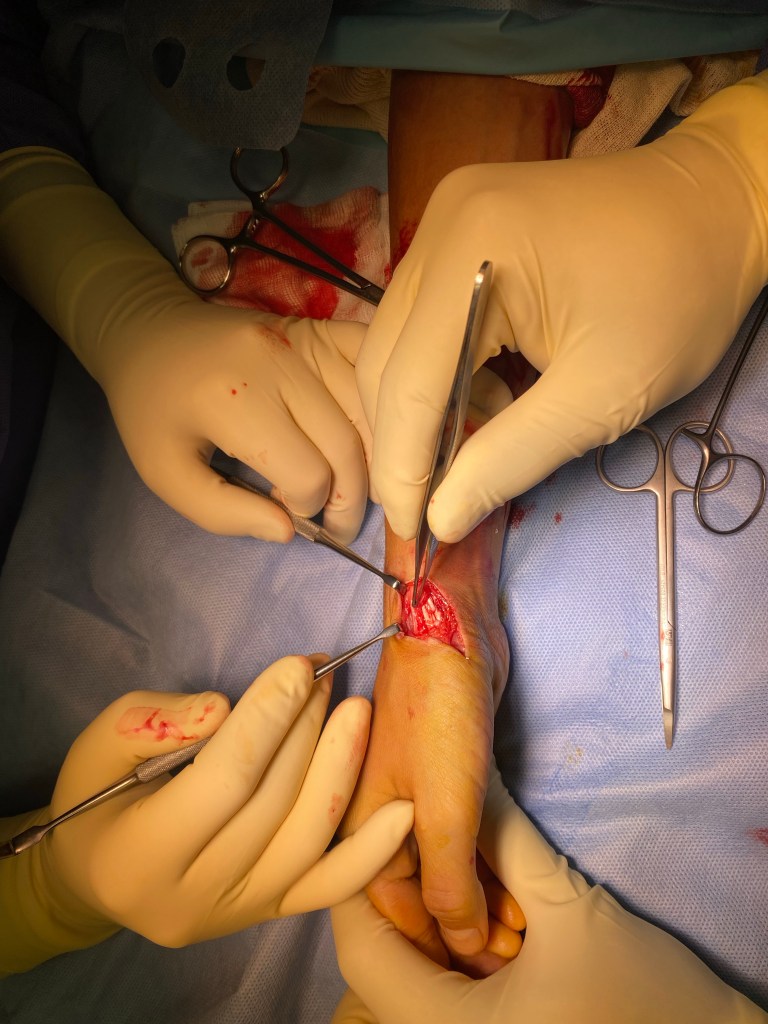

L’exploration d’une plaie consiste à rechercher des lésions des structures profondes et/ou des corps étrangers.

Elle peut être rendue nécessaire pas le caractère profond ou souillé de la plaie , des signes cliniques (saignement important , absence de sensibilité d’une zone) ou par la localisation de la plaie (la main est particulièrement riche en tendons nerfs et vaisseaux).

Pour cela, il est possible et fréquent que la plaie soit agrandie, afin de réaliser une vérification exhaustive.